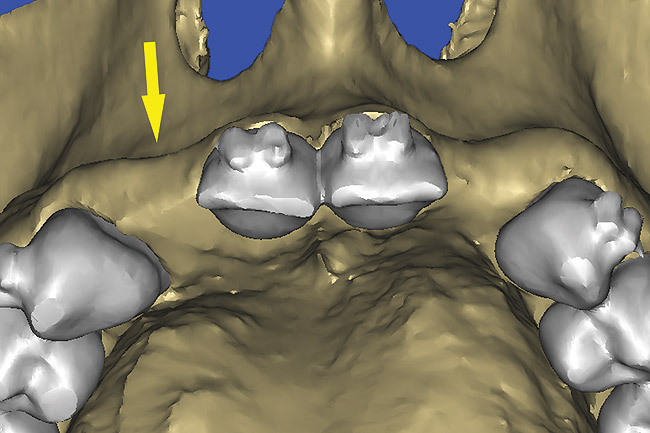

After the basic plan had been established, it was re-evaluated using interactive 3D images. The reconstructed 3D view of the maxilla clearly illustrated the extent of the bilateral facial concavities, and the root eminences of the adjacent and posterior teeth (Figure 12). The placement of the virtual implants then was evaluated to ensure that the facial cortical plate was not perforated (Figure 13). The implants were labeled individually as “7” and “10,” with the simulated yellow abutment projection indicating the facial-lingual inclination through the bone to the level above the incisal edge of adjacent teeth. The ability to gain a better understanding of these individual root forms cannot be underestimated. The dental literature has suggested certain parameters for placing implants near teeth and implants next to other implants. However, there is little scientific 3D documentation to support these suggested rules.5-10 The use of an interactive treatment-planning software application permits closer scrutiny of previously difficult-to-visualize areas, and can now be used to redefine perceptions of spatial positioning of implants, especially when in close proximity to natural tooth roots, vital anatomy, and adjacent implants.27-29

Figure 12  SOFTWARE IMAGING The 3D reconstruction showed the facial concavities and root eminences.

Figure 12

Figure 13  SOFTWARE IMAGING This allowed for evaluation of virtual implant placement to ensure the facial cortical plate was not perforated.

Figure 13